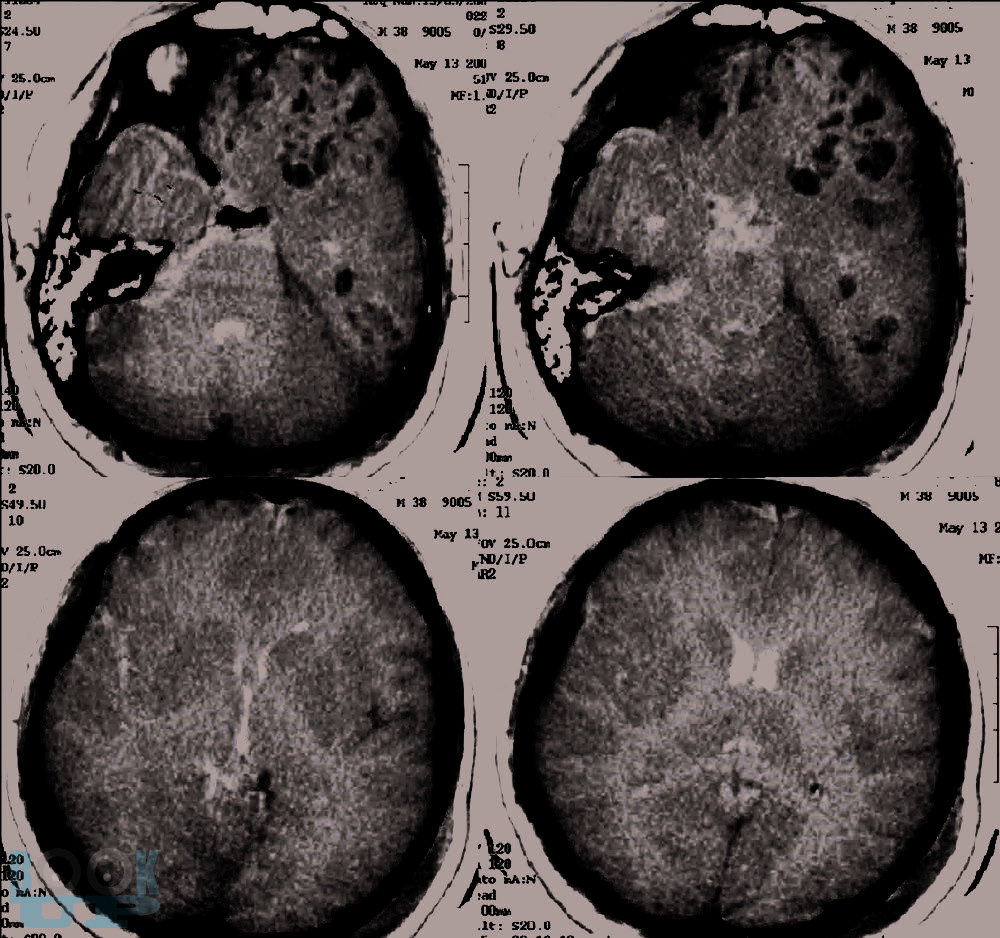

В этой книге мы рассказываем о динамике и взаимосвязи патологических процессов. Эти знания позволяют обосновать вашу тактику. В книге обсуждаются взаимосвязь первичного и вторичного повреждения мозга. Как внутричерепная гипертензия приводит к дислокациям и вклинениям головного мозга и/или нарушениям кровоснабжения мозга. Обсуждается регуляция тонуса сосудов мозга в норме и патологии. Зависимость церебрального перфузионного давления от среднего артериального давления, внутричерепного давления и сохранности ауторегуляции тонуса мозговых сосудов. Рассматриваем варианты отека мозга и возможности лечения. Мы рассказываем как на основе результатов мониторинга внутричерепного давления принимаются решения о том как лечить пациента.